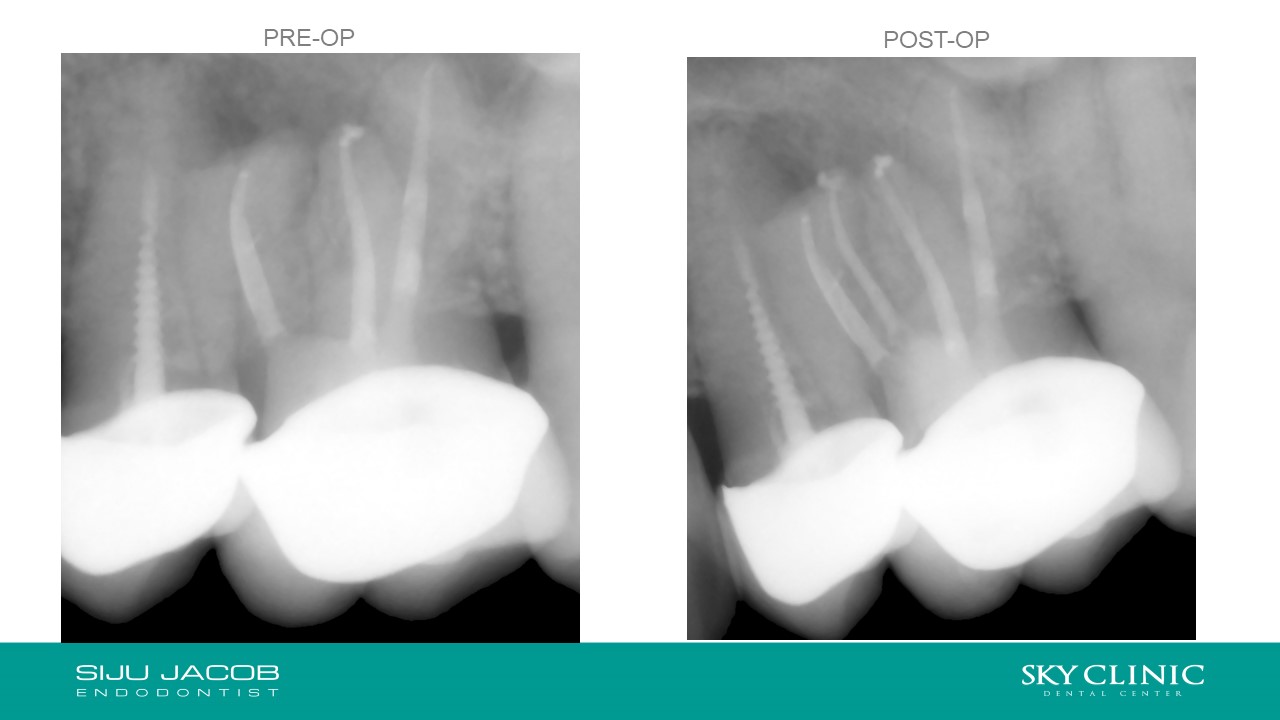

Selective Re-treat of Missed MB2